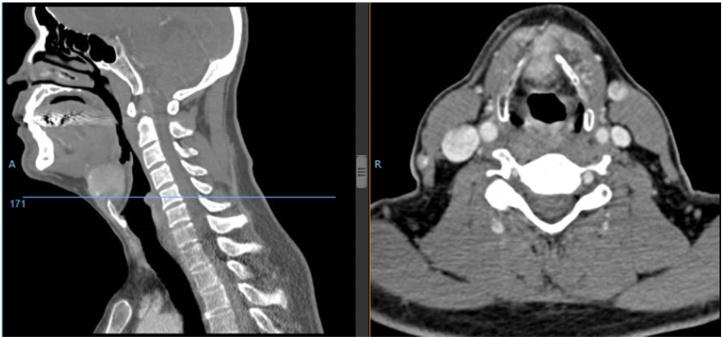

A 60 years old male patient, had a hard mass in the anterior neck. CT revealed a hyoid tumor. Hyoid bone resection was performed, the pathological report show a conventional papillary carcinoma in bone tissue. We rule out primary tumor in thyroid gland. Five years later, he developed a neck node recurrence. Total thyroidectomy and a selective left neck dissection (II-IV levels) was performed. He received radioiodine adjuvant treatment.

We propose to add a new subdivision to pathology derived from thyroglosal duct remnants). The diagnostic approach with ultrasound and CT are necessary. A primary in te hyoid gland mustang be discorded, and then the entire hyoid bone must be removed. Treatment of the thyroid gland and neck should be considered when there are significant risk factors of recurrence, similarly to thyroid cancer based on the risk assessment.